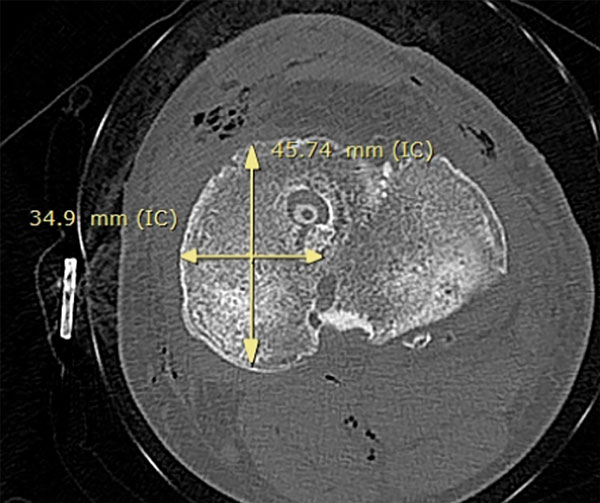

El tamaño meniscal a trasplantar se midió con el método radiográfico descripto por Pollard. El ancho se determinó utilizando la radiografía anteroposterior para medir la distancia entre el extremo anterior de la eminencia tibial y la periferia de la metáfisis tibial, y la longitud en una proyección lateral, midiendo el 80% de la longitud sagital de la meseta tibial, así como en cortes axiales tomográficos11 (figs. 4 y 5).

Figura 5: Medición del tamaño del TAM en corte axial tomográfico del platillo tibial.